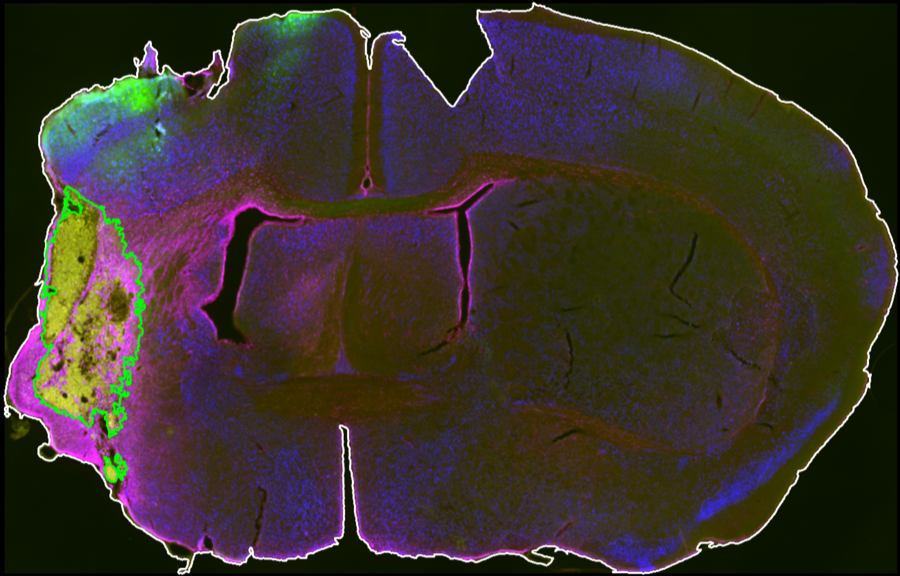

Segmentation Workflow

Interactive controls define midline placement, brain contour thresholds, CD68 thresholds, and exclusion-channel thresholds for section-level infarct segmentation.

Outputs

Analysis outputs include segmented infarct masks, merged review images, and CSV summaries saved per animal for quantitative comparison.